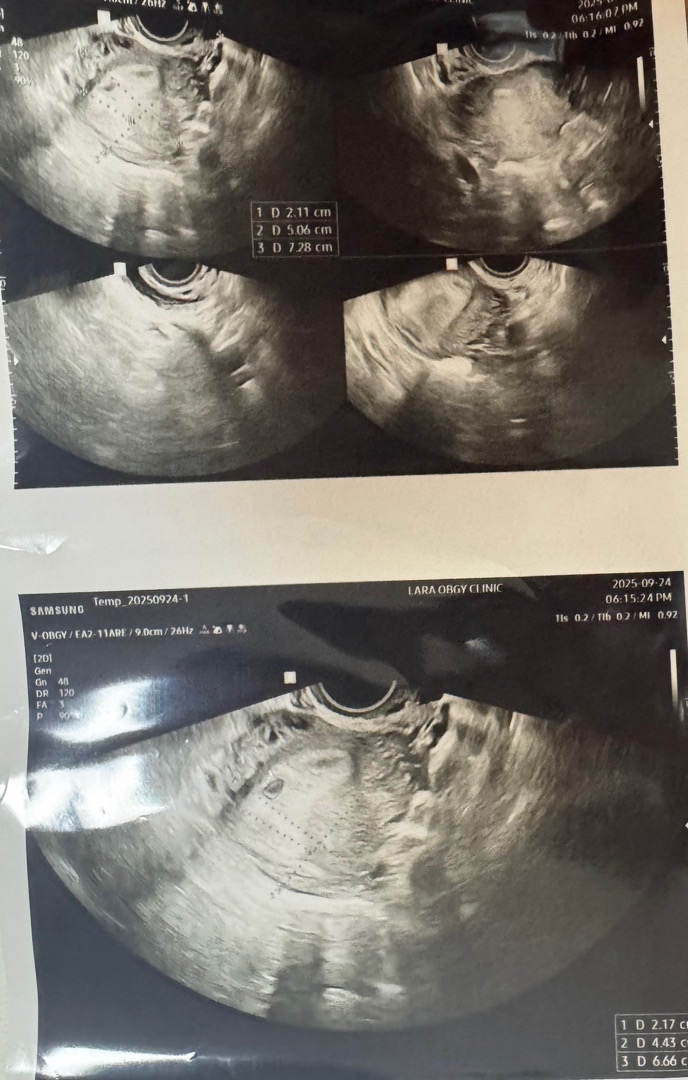

생리일 기준 4주 6일차에 안보여서 확인증 못받아보신분 있나요 ..?

원장님께서 계속 90프로 이상이긴한데 너무 작고 안보여서 확인증은 못준다는식으로 말씀 하시네요 ... ㅜㅜ 2주뒤에 오면 심장소리 들을수있을거라고 그때 오라구요 근데 그래서 아기가 생긴게 아닐수도 있는거냐구 하면 또 90프로 이상이라고 생각하라고 애매하게 얘기하시네요 ..! 이런 분 계신가용 ?